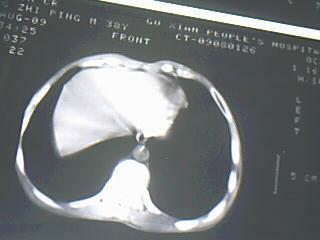

以下是引用随光逐影在2009-8-7 15:40:00的发言:[br]考虑右肺继发性肺结核并右肺上叶空洞形成,两肺支气管播散;不排除右肺上叶空洞内霉菌感染可能。

以下是引用jiangjing在2009-8-7 14:38:00的发言:[br]右上肺张力空洞,酐珞坏死灶,支气管扩张,多发播散灶,纵膈淋巴结显示,胸膜增厚---结核